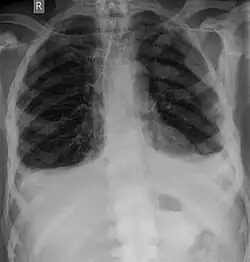

Pour le diagnostic initial, la radio X classique a une importance centrale. L'indication pour des projections sur deux plans est toujours donnée en cas de soupçon de tumeur osseuse[87]. Les métastases ostéolytiques sont caractérisées par une perte de densité osseuse. Ceci se reconnaît sur la radio par un noircissement plus élevé, en raison de la plus grande transparence aux rayons X. Inversement, les métastases ostéocondensantes présentent à cause de la plus grande densité osseuse un noircissement inférieur. Les métastases ostéolytiques sur la colonne vertébrale sont nettement plus difficiles à reconnaître : seulement quand environ 50 % de la densité totale de l'os a disparu[87].